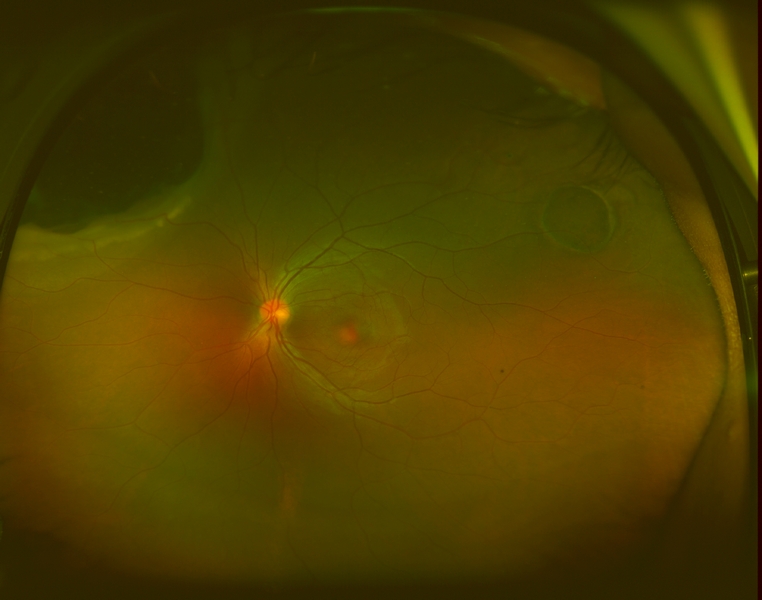

On exam, her visual acuity was 20/20 OD and 20/25 OS uncorrected. Intraocular pressures measured 16mmHg OU. Her external and anterior segment exam were unremarkable, with no evidence of inflammation. The posterior segment exam in the right eye was also unremarkable, with normal-appearing vitreous, optic nerve, macula, retinal vessels, and periphery. Examination of the left eye showed normal vitreous with no cells, normal optic nerve, and macula. In the supratemporal mid-periphery was a flat ~3 disc area CHRPE. In the supranasal periphery there was an irregular, elevated choroidal mass which involved 2 clock hours, which did not appear to extend anterior to the pars plana. The posterior aspect is anterior to the equator. The lesion was pigmented and there was trace hemorrhage overlying it. There was shallow subretinal fluid over the lesion and mild lipid exudation on its border.

Optos fundus photographs and fluorescein angiogram were performed. The angiogram showed early blockage with some mottled hyperfluorescence that increases in the later phase, with diffuse late leakage overlying the tumor.